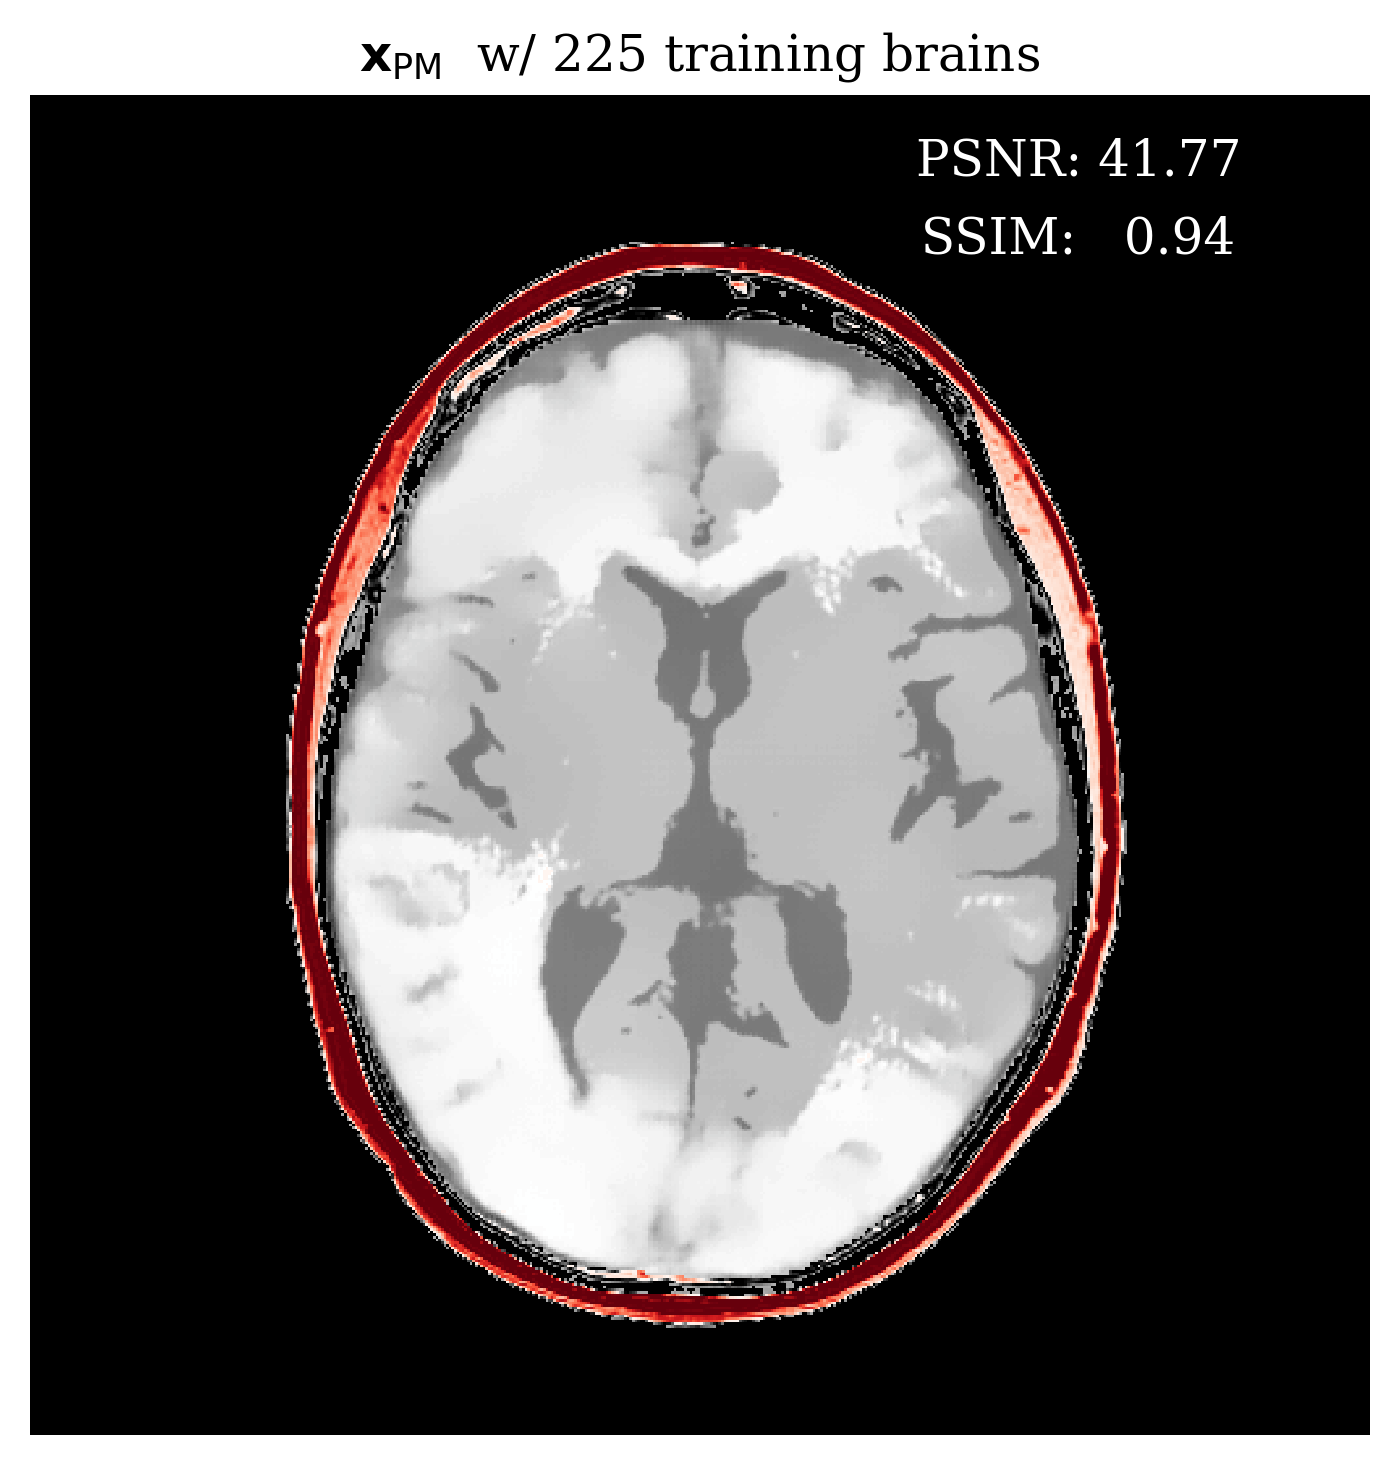

Since our method is Bayesian, its UQ results depend on how well it has learned the prior from training examples. In the case of conditional normalizing flows the prior is not explicitly accessible from the network since the network directly learns to sample the conditional distribution. Nonetheless, we would like to gain intuition on the effect of more training samples on the methods performance. In \figurereffig:trainingsize, we demonstrate the effect of increasing the training dataset size, on the posterior mean quality and on the UQ map that is produced. We observe from \figurereffig:trainingsize that as training samples increase, the posterior mean gets closer to the ground truth and that the UQ map becomes more contracted. These observations are similar to what happens when we increase the amount of observed data as explained in \sectionrefsec:uncertainty.

\subfigure

\subfigureUQ

\subfigureError

|